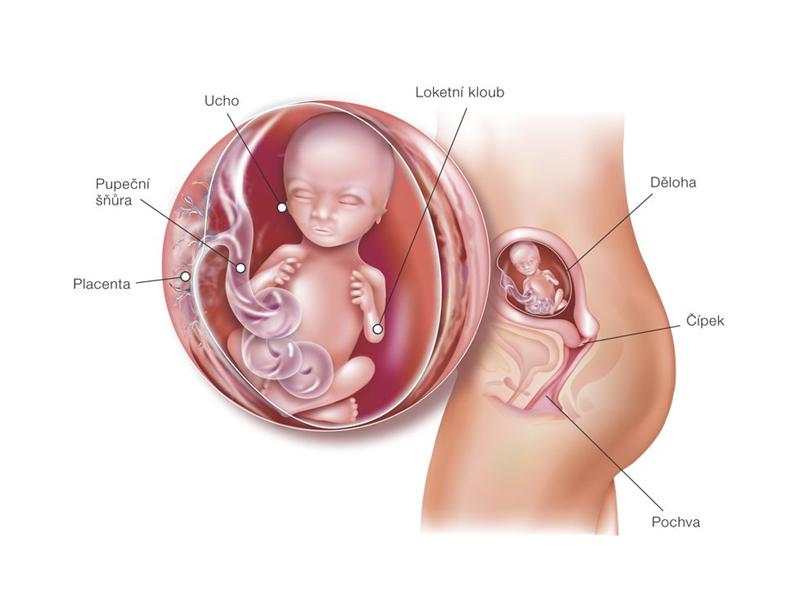

Vendy je v 39. týdnu těhotenství. Chcete vědět, co se děje s jejím tělem?